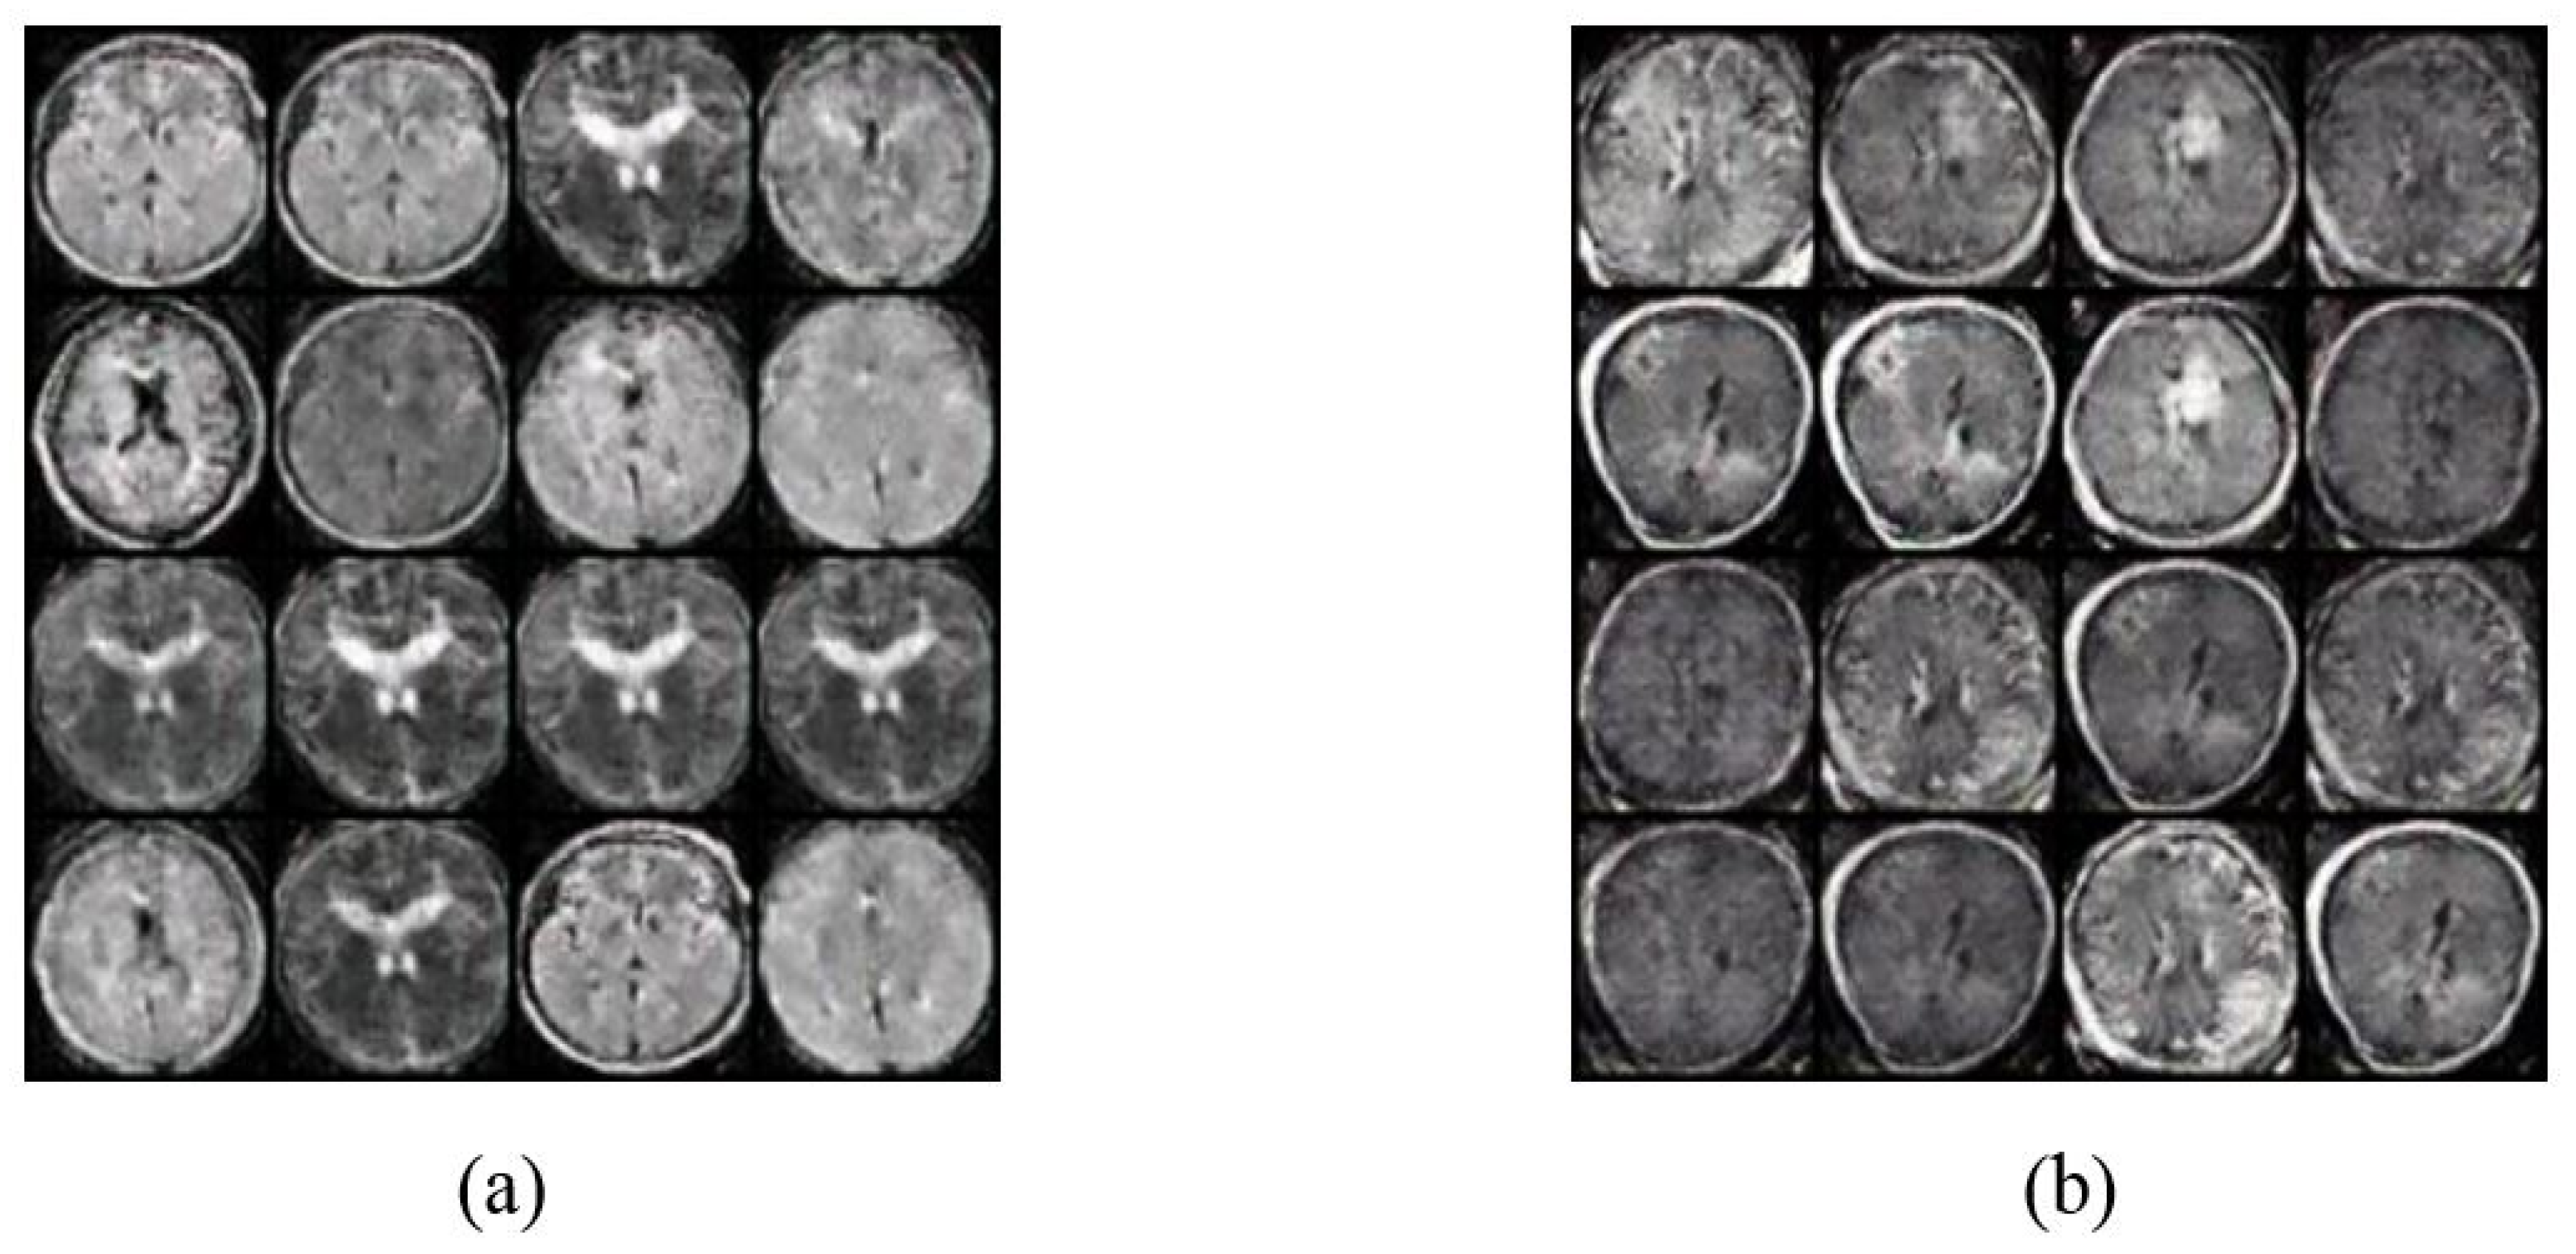

4.2. Image Augmentation Using Vanilla GAN and DCGAN

4.3. Deep Learning Proposed Classification Models